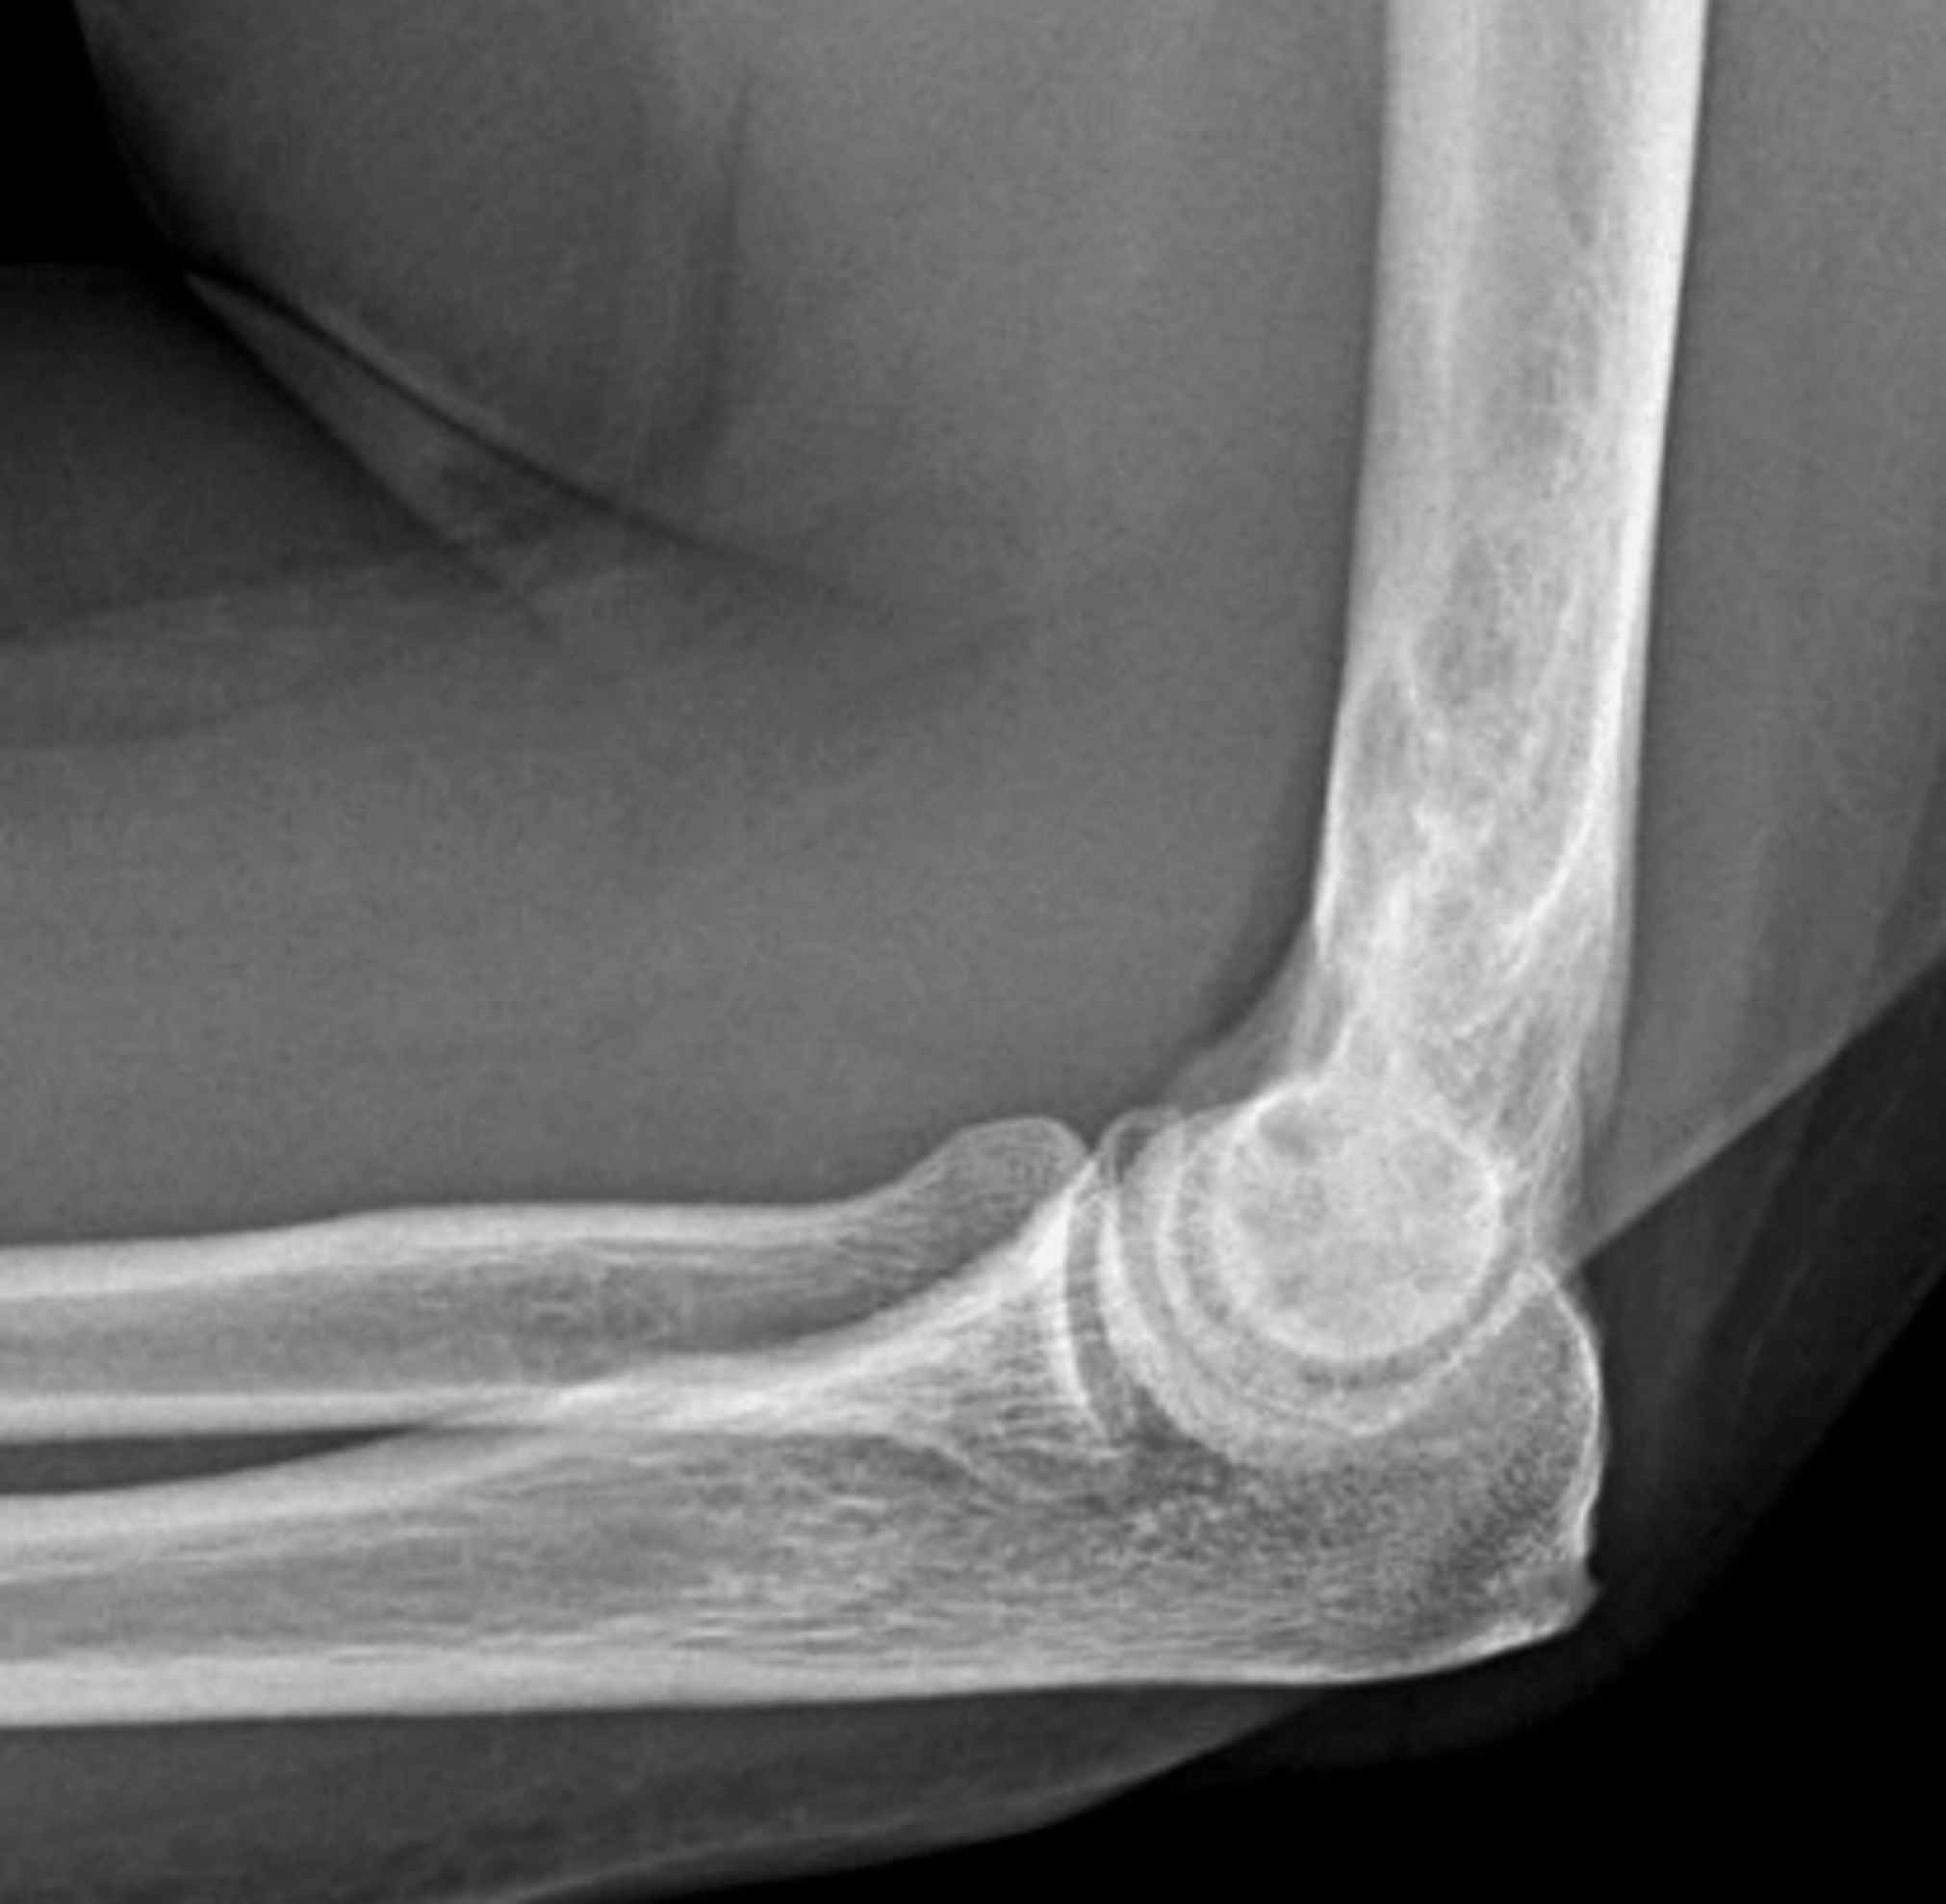

Figure 8: Mixed phase Paget disease in the distal humerus with atypical marrow replacement. (8A) AP and (8B) lateral elbow radiographs show classic findings of Paget disease in the distal humerus, including osseous enlargement, particularly of the medial epicondyle, with associated cortical and trabecular thickening. (8C) T1-weighted and (8D) STIR coronal images show diffusely abnormal marrow signal intensity in the medial humeral epicondyle (asterisks), hypointense compared to skeletal muscle on the T1-weighted sequence and uniformly hyperintense on the STIR sequence. This pattern of marrow replacement is atypical in uncomplicated Paget disease and prompted biopsy, which confirmed the diagnosis. Despite the marrow findings, the radiographic features in addition to the lack of osseous destruction and soft-tissue mass suggest uncomplicated Paget disease and fibrovascular changes. Short interval follow-up to document stability may obviate the need for biopsy in similar cases.